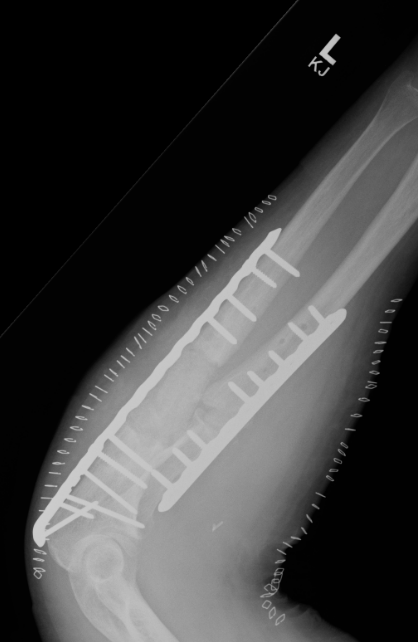

ORIF with DCP plates

Fixation with DCP plates

Options

Revision compression plating + drill intra-medullary canals + autograft

Results

- 35 forearm nonunions treated with revision compression plating and bone grafting

- average defect 2 cm

- 100% union